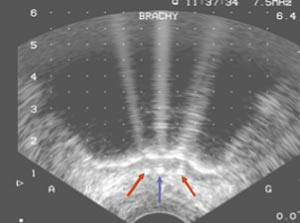

Frysingen kontrolleres med ultrasonografi. Man kan se at det dannes isballer rundt nåletuppene, isballer som etter hvert konfluerer. Isens ekspansjon mot rectum følges med spesiell oppmerksomhet (fig 4). Ved behov kan rectumveggen varmes med varmenålene, eventuelt med varmt vann som sprøytes inn via en sonde (3). Hvert område i prostata fryses i ti minutter. Frysesonen rundt nålene er 2,7 cm lang. For å fryse hele kjertelen må det som regel gjøres «pull back», der nålene trekkes tilbake i passende avstand for å fryse apikale del av prostata. Inngrepet varer omtrent to timer. Det gis antibiotikaprofylakse. Pasientene er som regel på beina og får mat samme kveld.